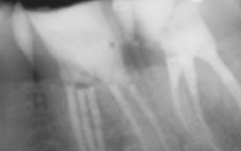

Dr Vinay Shah – Specialist Endodontist

Pre Op Radiograph

Post Op Radiograph